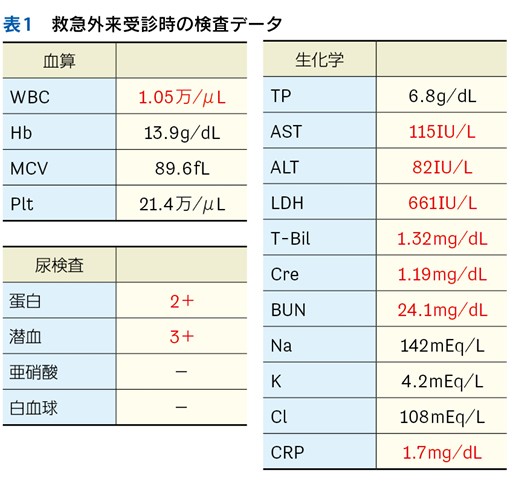

▶ semanticは直訳すれば「意味の」となるが,semantic qualifierを診断推論の文脈で訳すなら,「意味を限定する修飾語句」とでもなるだろう。先述のように,フレーミングに用いる問題を定義するにあたっては,個別具体的な情報は捨象され,抽象化・一般化された概念となっている必要がある。ゆえにSQも抽象的・一般的な医学用語に「翻訳」して表現する(表1)。